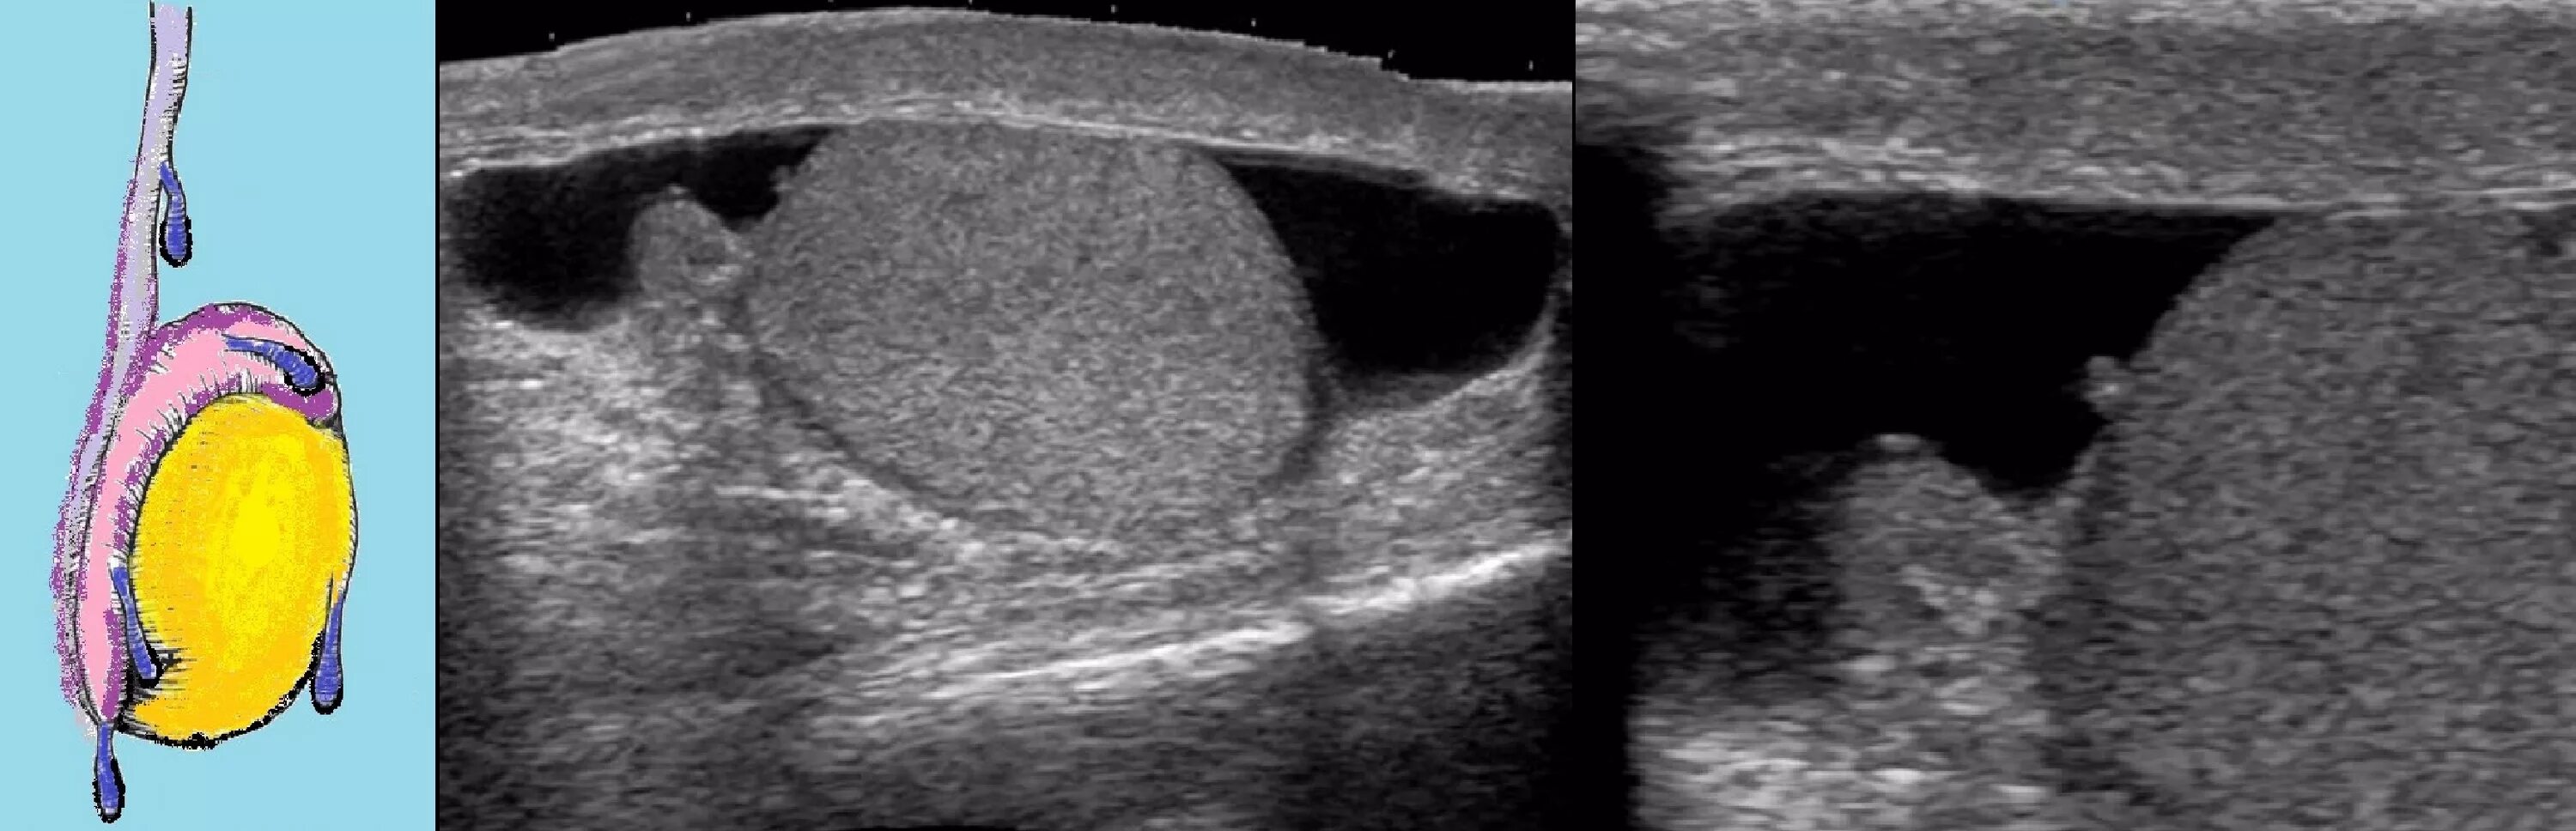

Обеих яичек